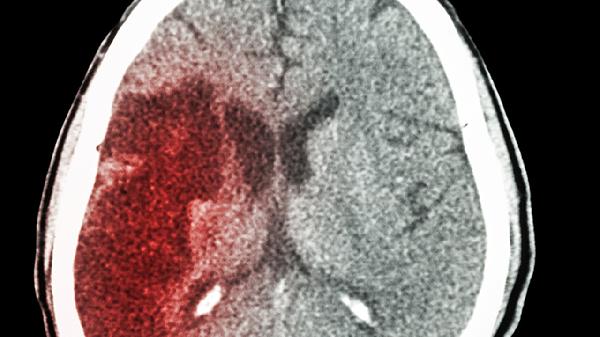

脑干、大面积半球梗死预后较差,可能影响吞咽和呼吸功能;而小范围皮层梗死对生存期影响较小。临床采用美国国立卫生研究院卒中量表评估严重程度,评分越高预后越不乐观。